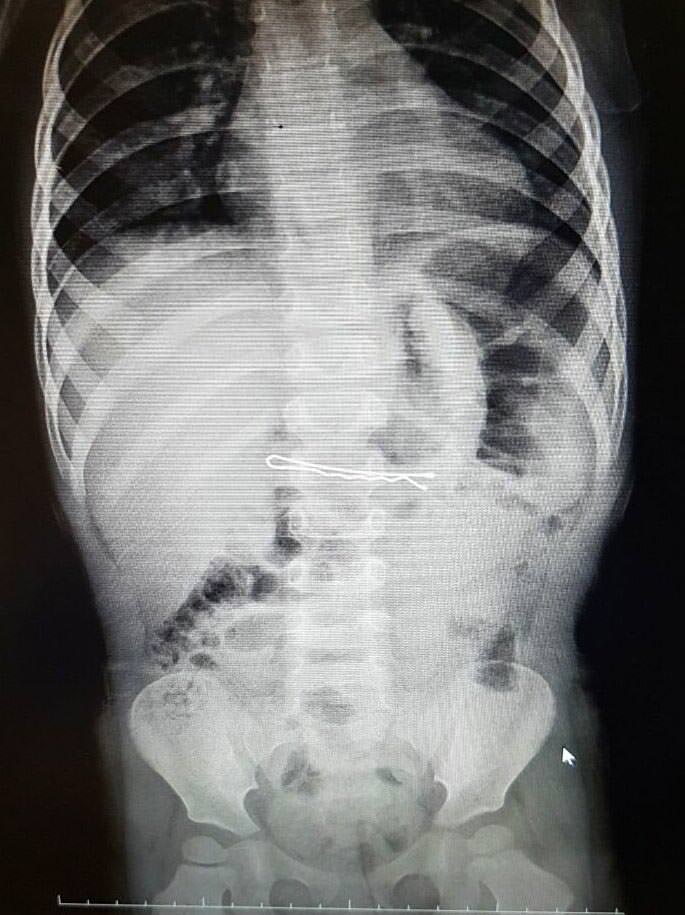

İzmir'deki Tepecik Eğitim ve Araştırma Hastanesi Çocuk Gastroenteroloji Bölümü'nün, yabancı cisim yutan çocukların nefes ve borusu ile midelerinden çıkarttığı, anahtarlık, madeni para, saat pili, ataç, çengelli iğne ve çivi gibi objeler görenleri şaşkına çevirdi.

"Çocukların nefes ve borusu ile midelerinden çıkartılan, anahtarlık, madeni para, saat pili, ataç, çengelli iğne ve çivi gibi objeler görenleri şaşkına çevirdi. "